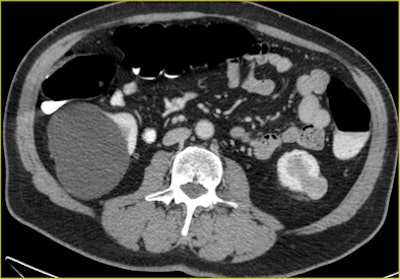

| A 70-year-old man underwent CTC after incomplete colonoscopy at the transverse colon showing a large stenotic lesion in the splenic flexure with bleeding and high-grade dysplasia. CT colonography revealed dolichocolon, a second stenotic lesion in the sigmoid colon, and a tumor in the left kidney, precluding a laparoscopic approach. All images courtesy of Dr. Riccardo Rizzeti. |